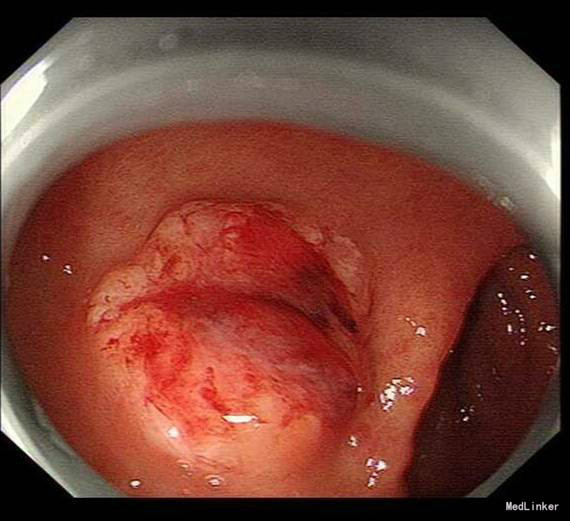

患者,男性,69岁,间歇性中上腹隐痛1月,加剧1周来我院门诊就诊,胃镜检查:见胃窦前壁处可见一1.5*2.0cm粘膜隆起,表面粗糙,见图1,胃镜诊断:胃窦粘膜隆起(性质待病理),慢性浅表性胃窦炎伴胆汁反流,10月26日门诊病理:胃窦:慢性萎缩性胃炎,急性活动,伴部分腺体中重度不典型增生,局灶重度不典型增生。于2015年10月28日入院。

诊疗经过:入院后经过术前检查,行放大内镜检查和超声内镜检查,超声内镜提示:胃窦病灶未突破粘膜下层,诊断考虑:胃早癌。于10月30日行内镜下胃ESD术,术顺,安返病房。经过过制酸、补液等对症处理,3天后患者顺利出院。

随访:出院后2周,电话随访患者,一般情况良好,无不适主诉。 讨论:该患者胃镜见一胃窦前壁粘膜隆起,表面粘膜粗糙,病理示:慢性萎缩性胃炎,伴部分腺体中重度不典型增生,局灶重度不典型增生,超声胃镜病灶未突破粘膜下层,有胃ESD手术指征,故行全麻下胃ESD术。术后病理:胃窦前壁肿瘤:腺上皮高级别上皮同瘤,部分癌变,病变大小1.5*1.1*0.3cm,基底及切缘未见癌。说明手术成功,切缘及基底均无肿瘤侵及。对于早癌患者我们完全可以通过采用ESD方法治愈患者,胃镜下切除早癌较腹腔镜创伤更小。我和患者解释时是这样说的:腹腔镜是微创,而我们内镜下ESD则是微微创。